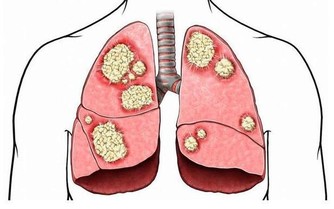

陳 昌平說明大腸癌的成因:「簡單說,是先有便祕,接著產生息肉,再病變成大腸癌。」大腸是由升結腸、橫結腸、降結腸及乙狀結腸等所構成,左側的大腸管徑比右 側大腸窄,當有腫瘤發生時,就會出現腸阻塞而引起便祕、腹脹甚至腹痛的情形。因為糞便大多在左側的結腸成形,因此如果阻塞的狀況嚴重的話,所排出的糞便就 會有時還會參雜血絲, 嚴重到便祕及解血便情形。

陳昌平認為,大腸癌的成因與飲食最有關係,其次是遺傳,因此經常大魚大肉或有家族病史者,一定要 每年接受檢查,及早發現及早治療。許多研究皆顯示,攝取過多的動物性脂肪會增加罹患大腸癌的機會,因此應多吃高纖食物,食物纖維有助於吸收腸內水分,使糞 便體積增大,刺激腸子蠕動,方便排泄,避免便祕且縮短致癌物質留在腸內的時間,降低罹癌機率。